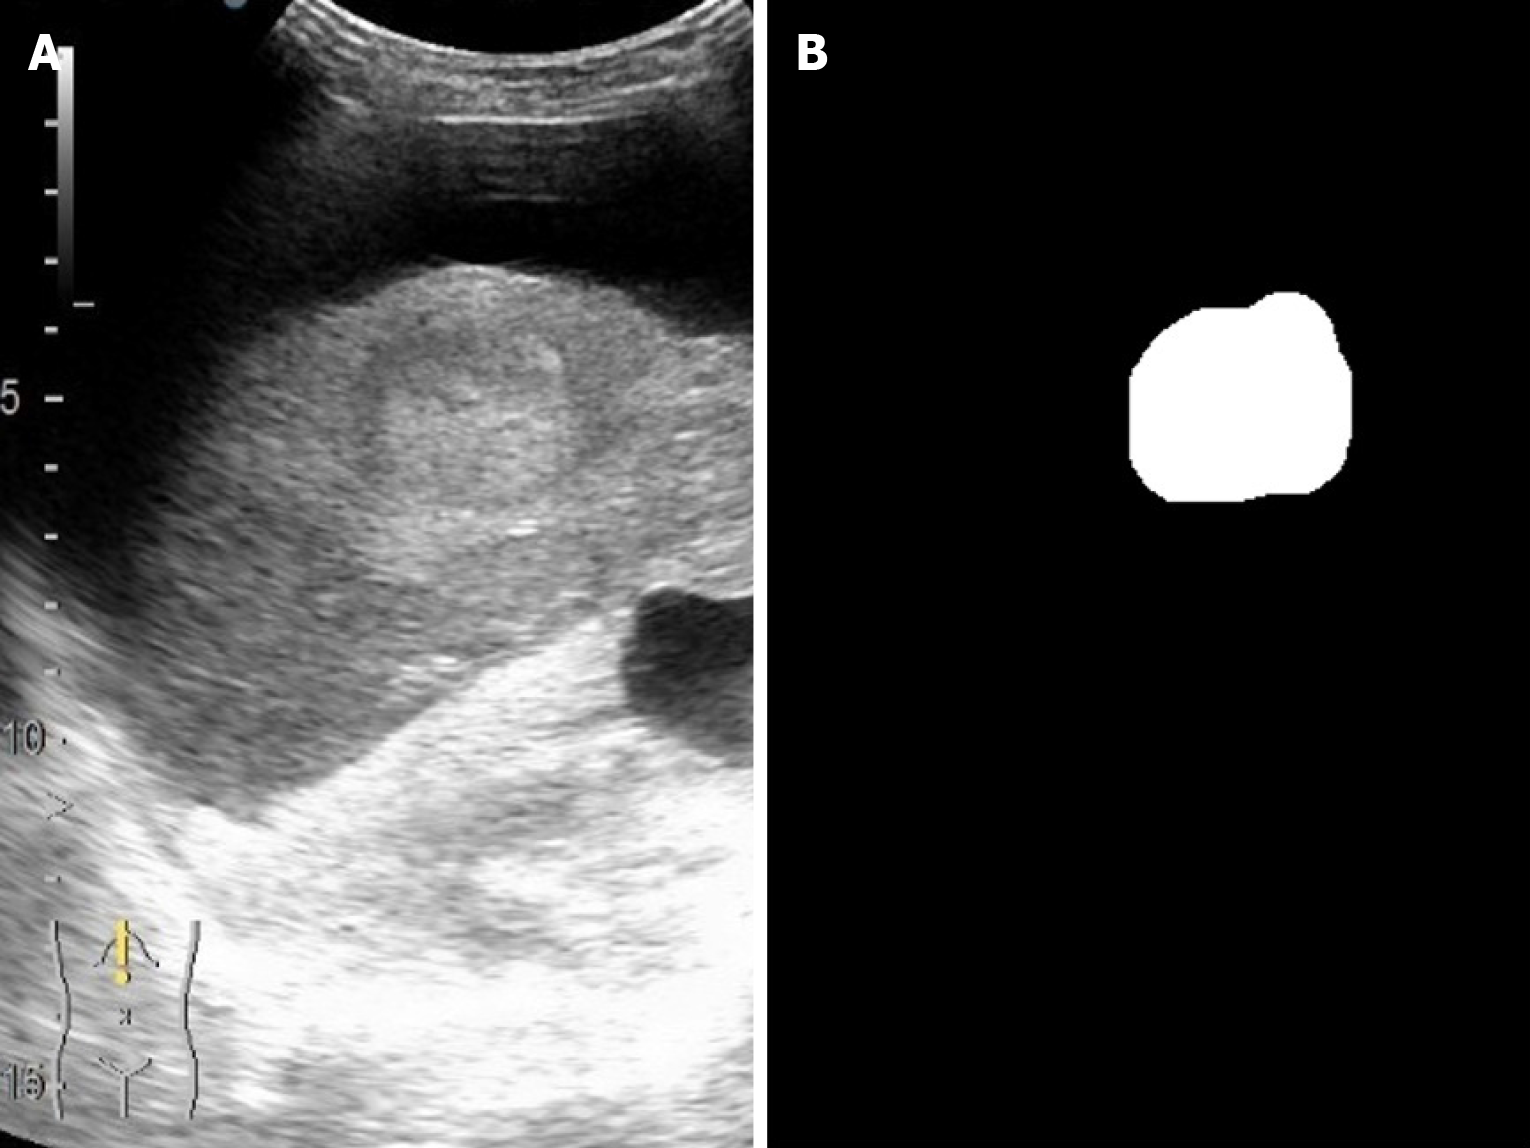

Figure 2 Representative contrast-enhanced ultrasound B-mode frame with expert lesion annotation.

The grayscale B-mode ultrasound image shows a focal liver lesion (outlined by the expert’s manual annotation in the B-mode field) that serves as the segmentation target. The corresponding binary mask (segmentation label) highlights the lesion region (distinguished from normal tissue) and provides the ground truth for training the deep learning model.